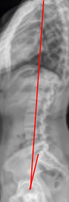

X-Ray

Full Length Spine

Coronal Balance

Apical Vertebral Translation (AVT)

Cobb Angle